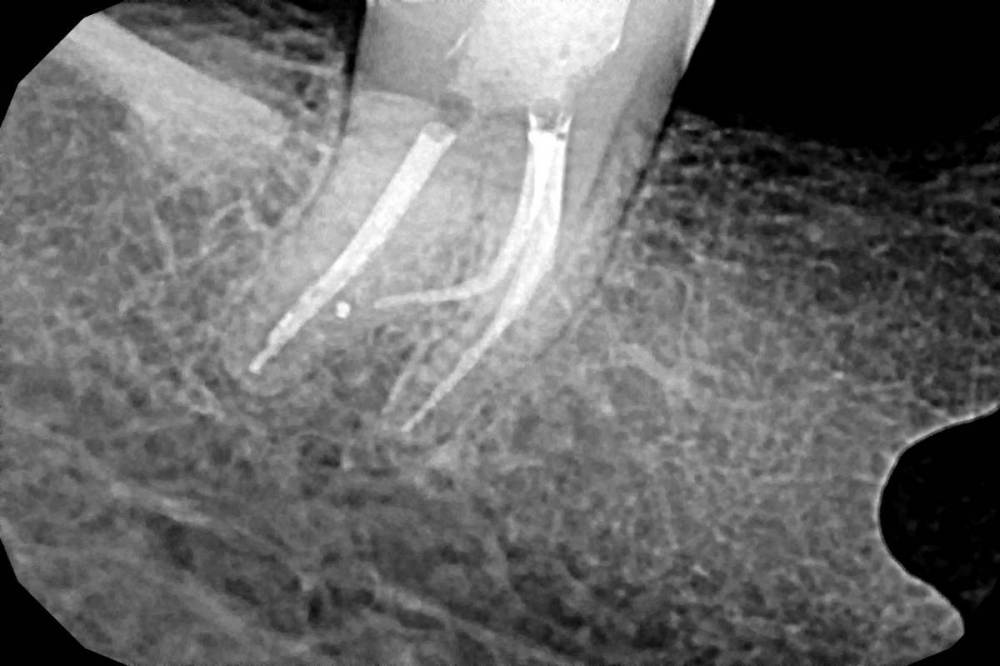

Ico Опубликовано 29 апреля, 2022 Автор Поделиться Опубликовано 29 апреля, 2022 Необратимый пульпит 47,я редко такой изгиб язычного видел. Префлеринг S1-S2(21 мм),скаут 8-10,патфаилы. Нитифлекс на 25к финиш 25.04 профаил.Мартенсита на то время не было.Паковка волна с эйчем. 5 Ссылка на комментарий